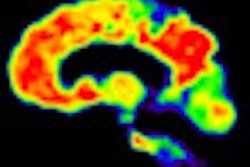

Until this study, PiB-PET has primarily been known for its utility in detecting biomarkers that are early signs of several forms of dementia. PiB has detected deposits of amyloid plaque in the human brain, which have been associated with the onset of Alzheimer's disease.